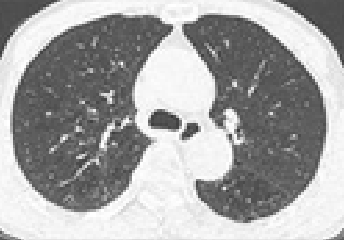

석면폐증(잠복기 약 15~40년)

잠복기가 약 15~40년에 걸친 석면으로 인한 석면폐증에 대한 CT사진

석면에 의한 폐 조직에 상처로 나타나는 폐섬유화 증상

• 폐의 섬유화로 희게 나타나며 공기집이 생겨 벌집모양으로 나타남

석면폐증의 병 유형(의심형, 초기형, 진행형) 및 폐기능 장해단계(정상, 경도장해, 고도장해)에 따라 1~3급으로 구분

• 석면폐증의 병 유형 : 폐섬유화 소견에 따라 의심형, 초기형, 진행형으로 구분

폐섬유화 소견에 따른 의심형 이미지 〈의심형〉

폐섬유화 소견에 따른 초기형 이미지 〈초기형〉

폐섬유화 소견에 따른 진행형 이미지 〈진행형〉